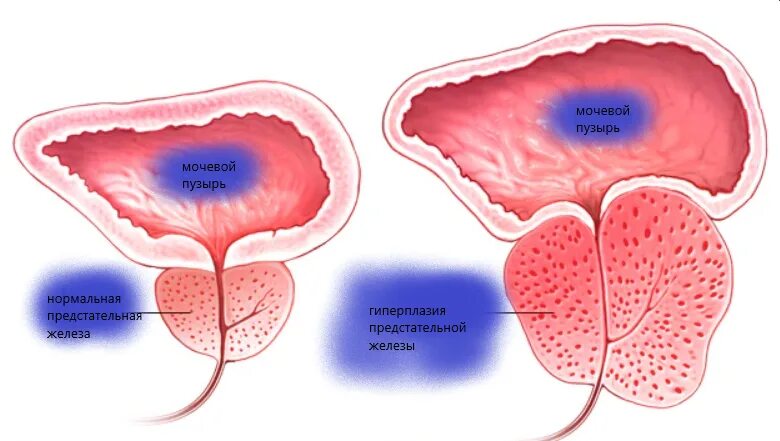

Диффузные предстательной железы